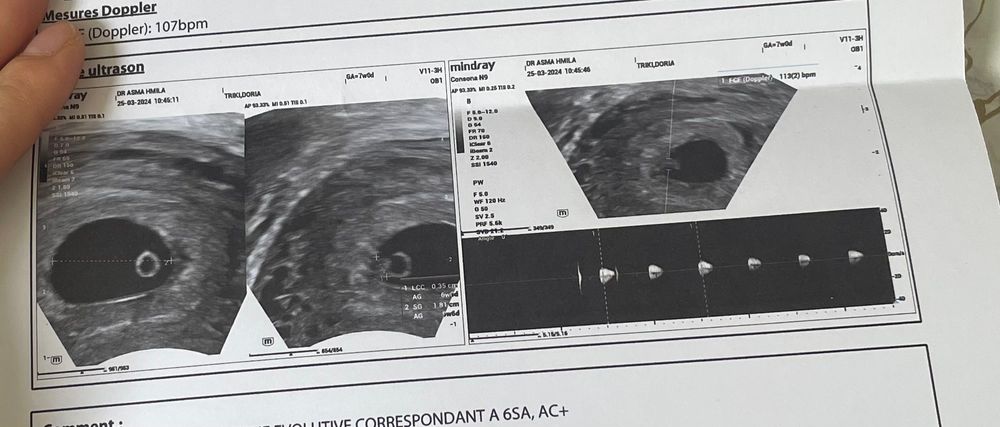

Беременность 6 недель

УЗИ, КТГ, доплер

сегодня ходили на 2 узи ( первое делала на 4-5 неделе) и наконец нашли эмбрион и сердцебиение 🥰 сказали все хорошо , но так же нашли кисту на левом яичнике (3мм) , врач сказала не страшно , сама рассосется , но прописала утрожестан свечи . У кого была киста и как протекала беременность ?🤰